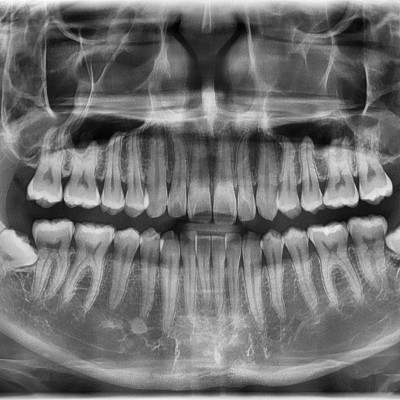

#18,48 사랑니 발치 #18,48 사랑니 발치 구강 외과 전문의가 당일 발치했습니다. ------------------------..

작성자 이턱이 작성일 03-11 조회 48